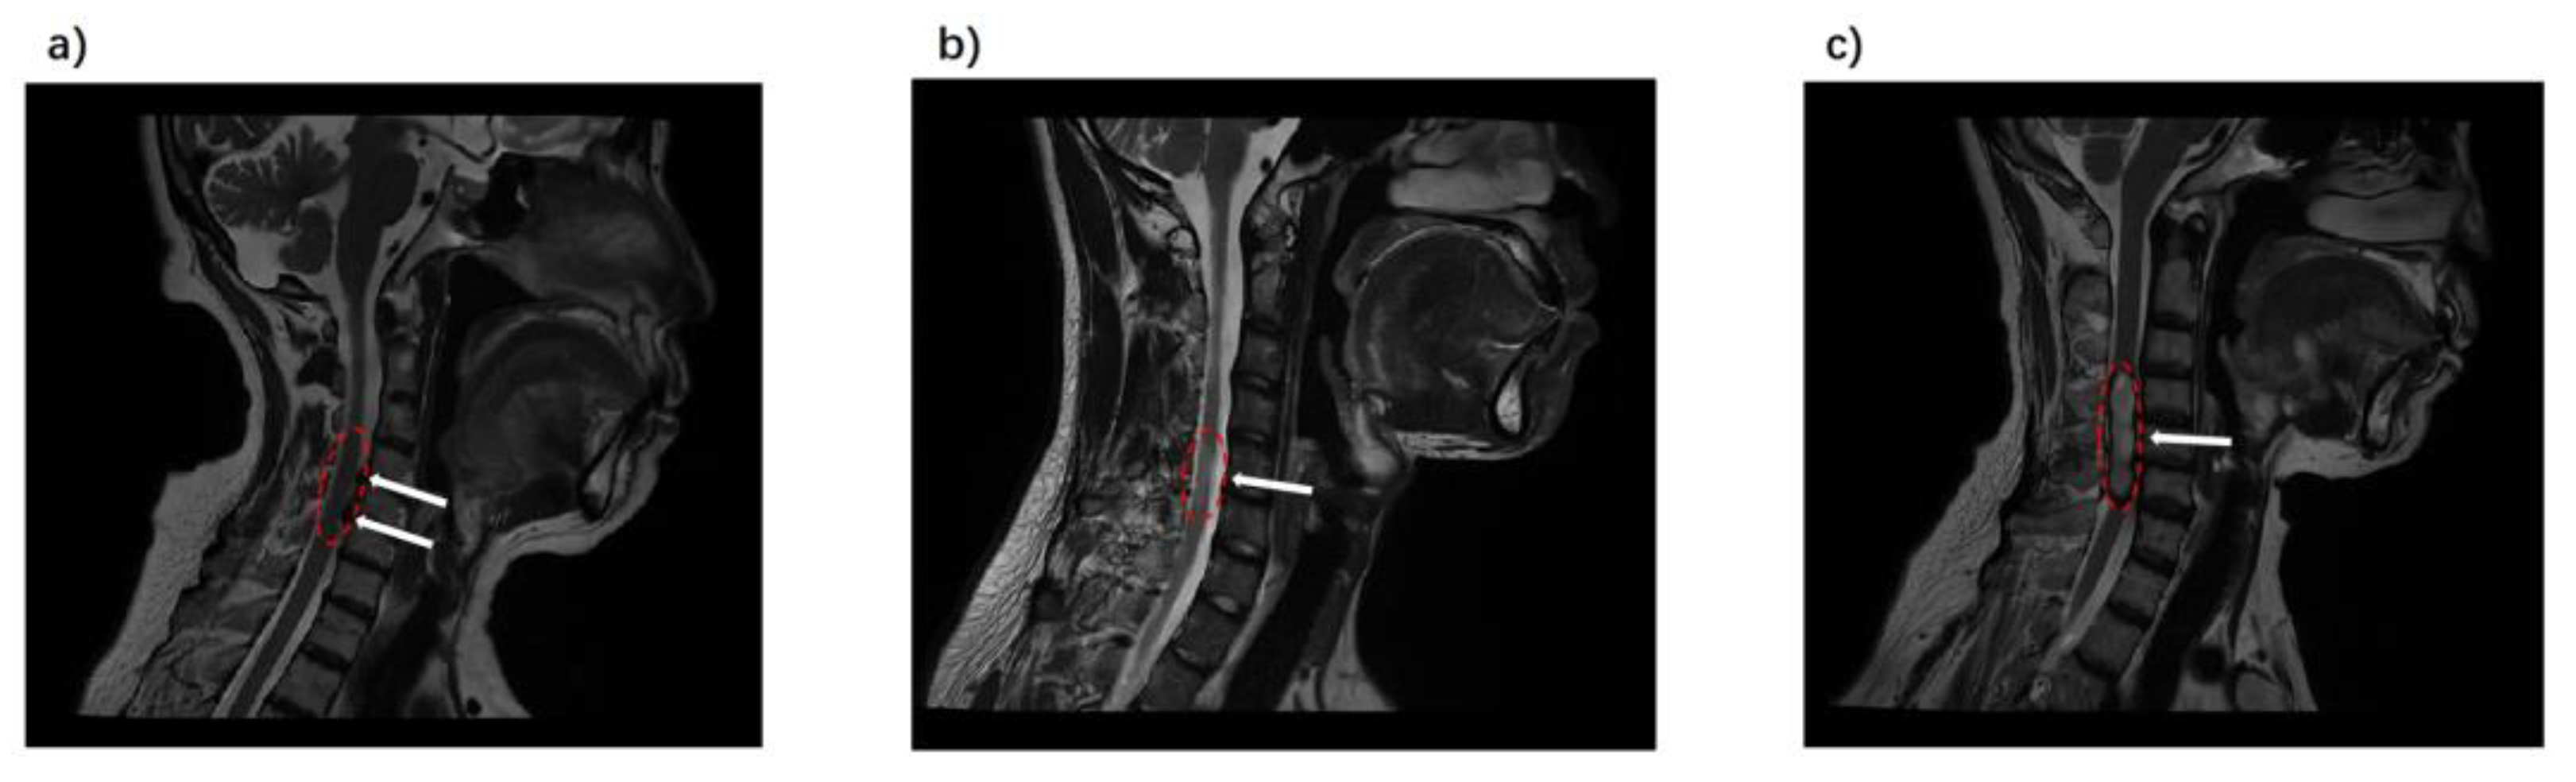

3.2. DTI Indicators in Spondylosis, Myelitis, and Spinal Tumors

3.3. Discriminative Power of DTI Indicators in Spinal Pathologies